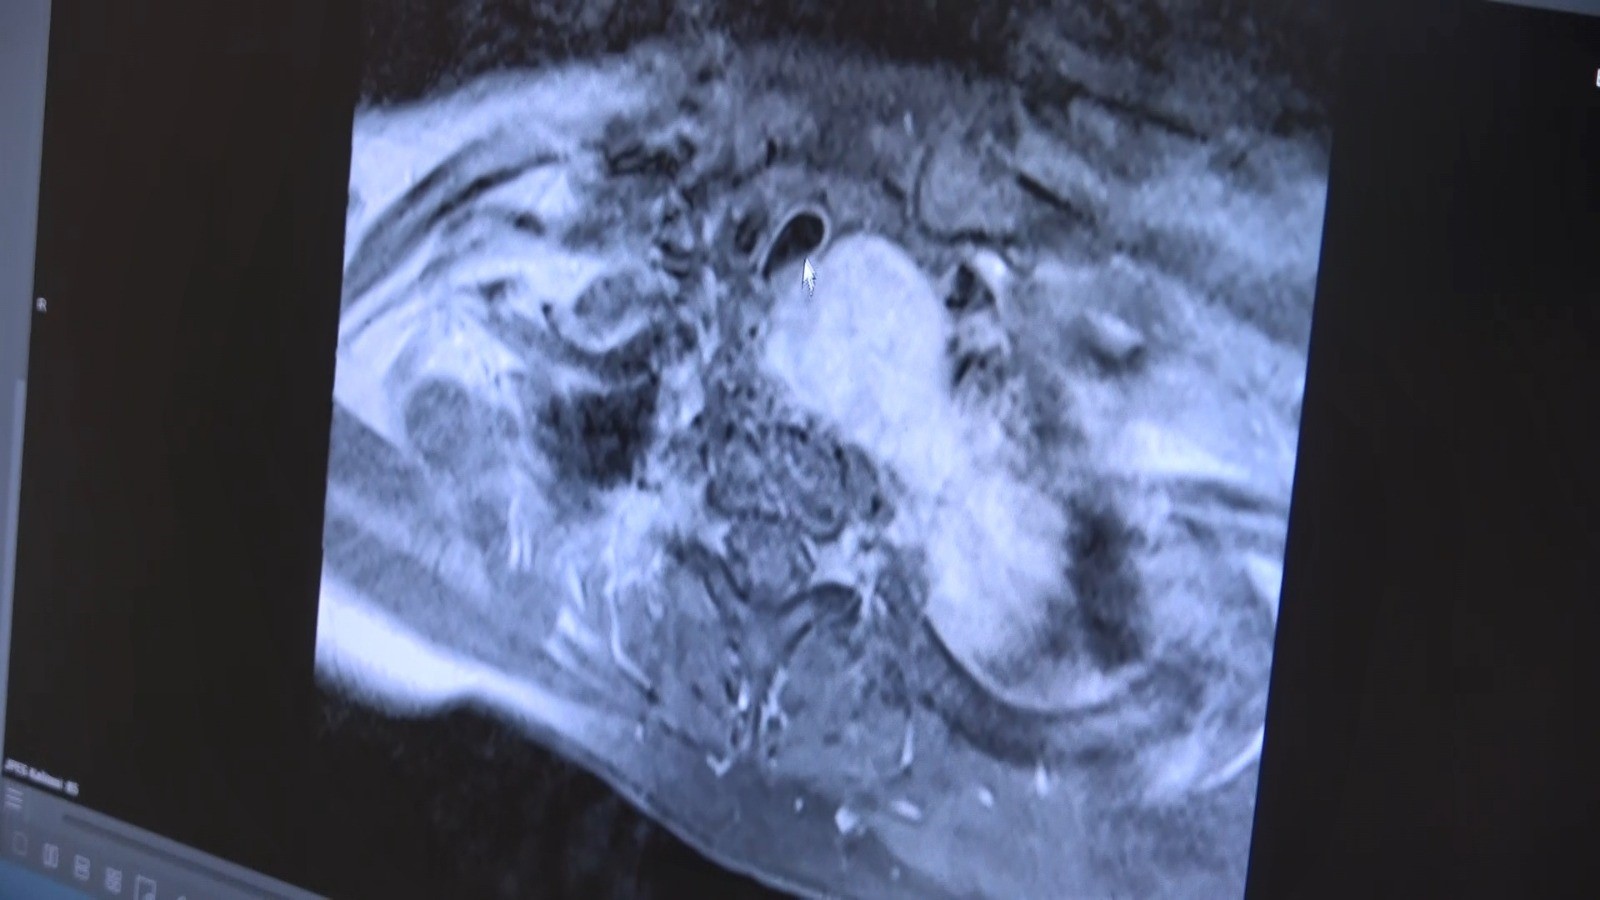

Prof. Dr. Güven Olgaç, “Hastamız bize başlıca nefes darlığı, yutma güçlüğü ve ciddi sırt ağrısı şikâyetleri ile başvurdu. Yaptığımız tetkikler sonucunda boyun bölgesinden başlayıp kalbine ve sırt omurlarına kadar uzanan, aynı zamanda nefes borusu ile yemek borusuna ciddi baskı oluşturan 12 santimlik bir kitle tespit ettik. Aldığımız biyopsi bize bu tümörün ‘iyi huylu’ olduğunu gösterdi ve hayati organlarda oluşturduğu ciddi baskı semptomları nedeniyle en iyi tedavi şeklinin cerrahi yöntem olduğunu bildiğimiz için ameliyat önerdik. Prof. Dr. Keramettin Aydın’ın önderliğinde Beyin Cerrahisi ekibimizin de katkıları ile beraber bu operasyonu gerçekleştirdik. Biz kitleyi şah damarı, kalp, akciğer, soluk borusu ve yemek borusundan ayırdıktan sonra beyin cerrahisi ekibimiz, kitlenin omurga ile olan yapışıklığını giderecek şekilde bir ameliyat gerçekleştirdi. Çok şükür, ameliyatı gayet başarılı oldu ve 10 gün içerisinde hastamızı taburcu ettik. Gülsüm şimdi ameliyat sonrası 3. ayında ve artık normal hayatına döndü diyebiliriz. Yaptığımız kontrollerde tümörün tamamen alınmış olduğunu ve önceden tümör basısına maruz kalan tüm hayati organların normale döndüğünü gördük” şeklinde konuştu.

“Omurgaya uzanan bölgede portakal büyüklüğündeki tümörün tamamını çıkardık”

Beyin ve Sinir Cerrahisi Kliniği’nden Prof. Dr. Keramettin Aydın ise “Göğüs cerrahisi kliniği ile birlikte yaptığımız incelemelerde, kalbin arkasında omurgaya uzanan bölgede yaklaşık bir portakal büyüklüğünde kitle olduğunu gördük. Dünya Tıp literatüründe son derece nadir rastladığımız bu ameliyatı Göğüs Cerrahisi ekibimiz ile birlikte planladık. Ameliyat sırasında önce göğüs ön duvarını açtık ve daha sonra sırt bölgesinden 'torakotomi' dediğimiz ek bir yaklaşımla tümörün omurga ile ilişkisini ortaya koyduk. Öngördüğümüz gibi tümörün sinir kaynaklı olduğunu tespit ettik ve ilişkili omurgaların sadece bir kısmını temizleyerek tümörün tamamını çıkarmamız mümkün oldu. Böylece hastamızın omurgasına, daha sonraki yaşamında sırt hareketlerini kısıtlayacak bir platin desteği koymak zorunda kalmadık. Multi-disipliner ‘çok-disiplinli’ yaklaşımla gerçekleştirdiğimiz bu ameliyat, bu yönüyle de bizim için çok tatmin edici oldu ve hastamız şu anda, aktif günlük yaşamını olumsuz etkileyen herhangi bir hareket kısıtlılığı olmaksızın normal şekilde yaşantısını sürdürebiliyor” açıklamalarında bulundu.